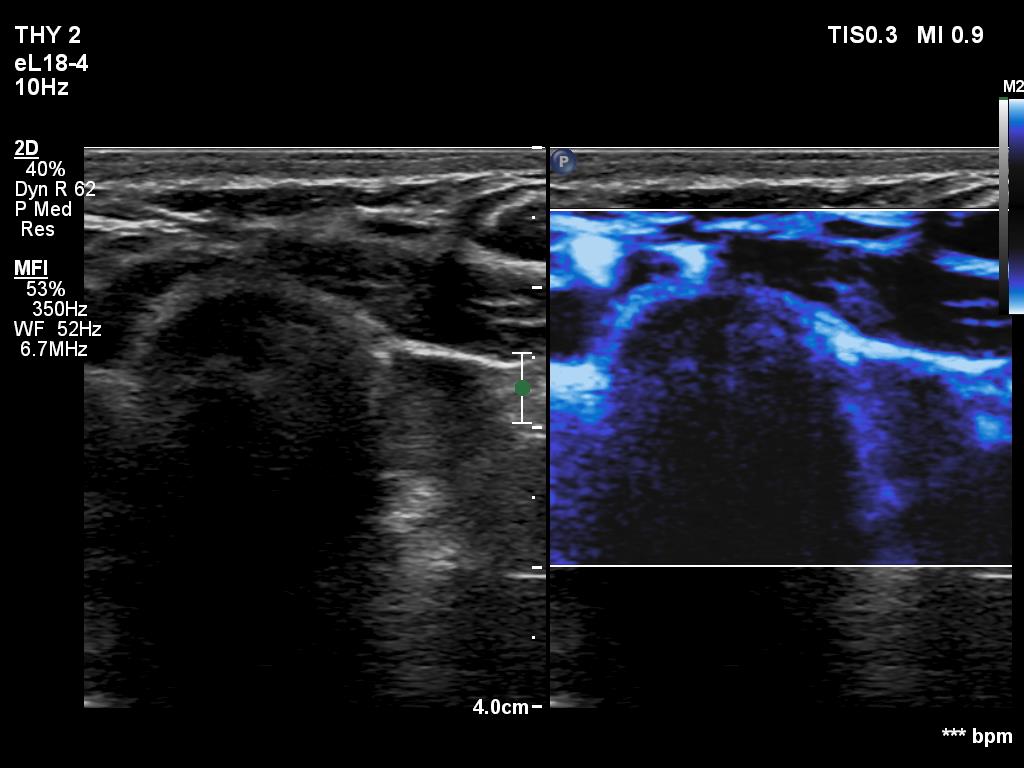

Right lobe, longitudinal scan

Left thyroid bed, transverse scan, microflow imaging. The lesion has a few if any vessels.